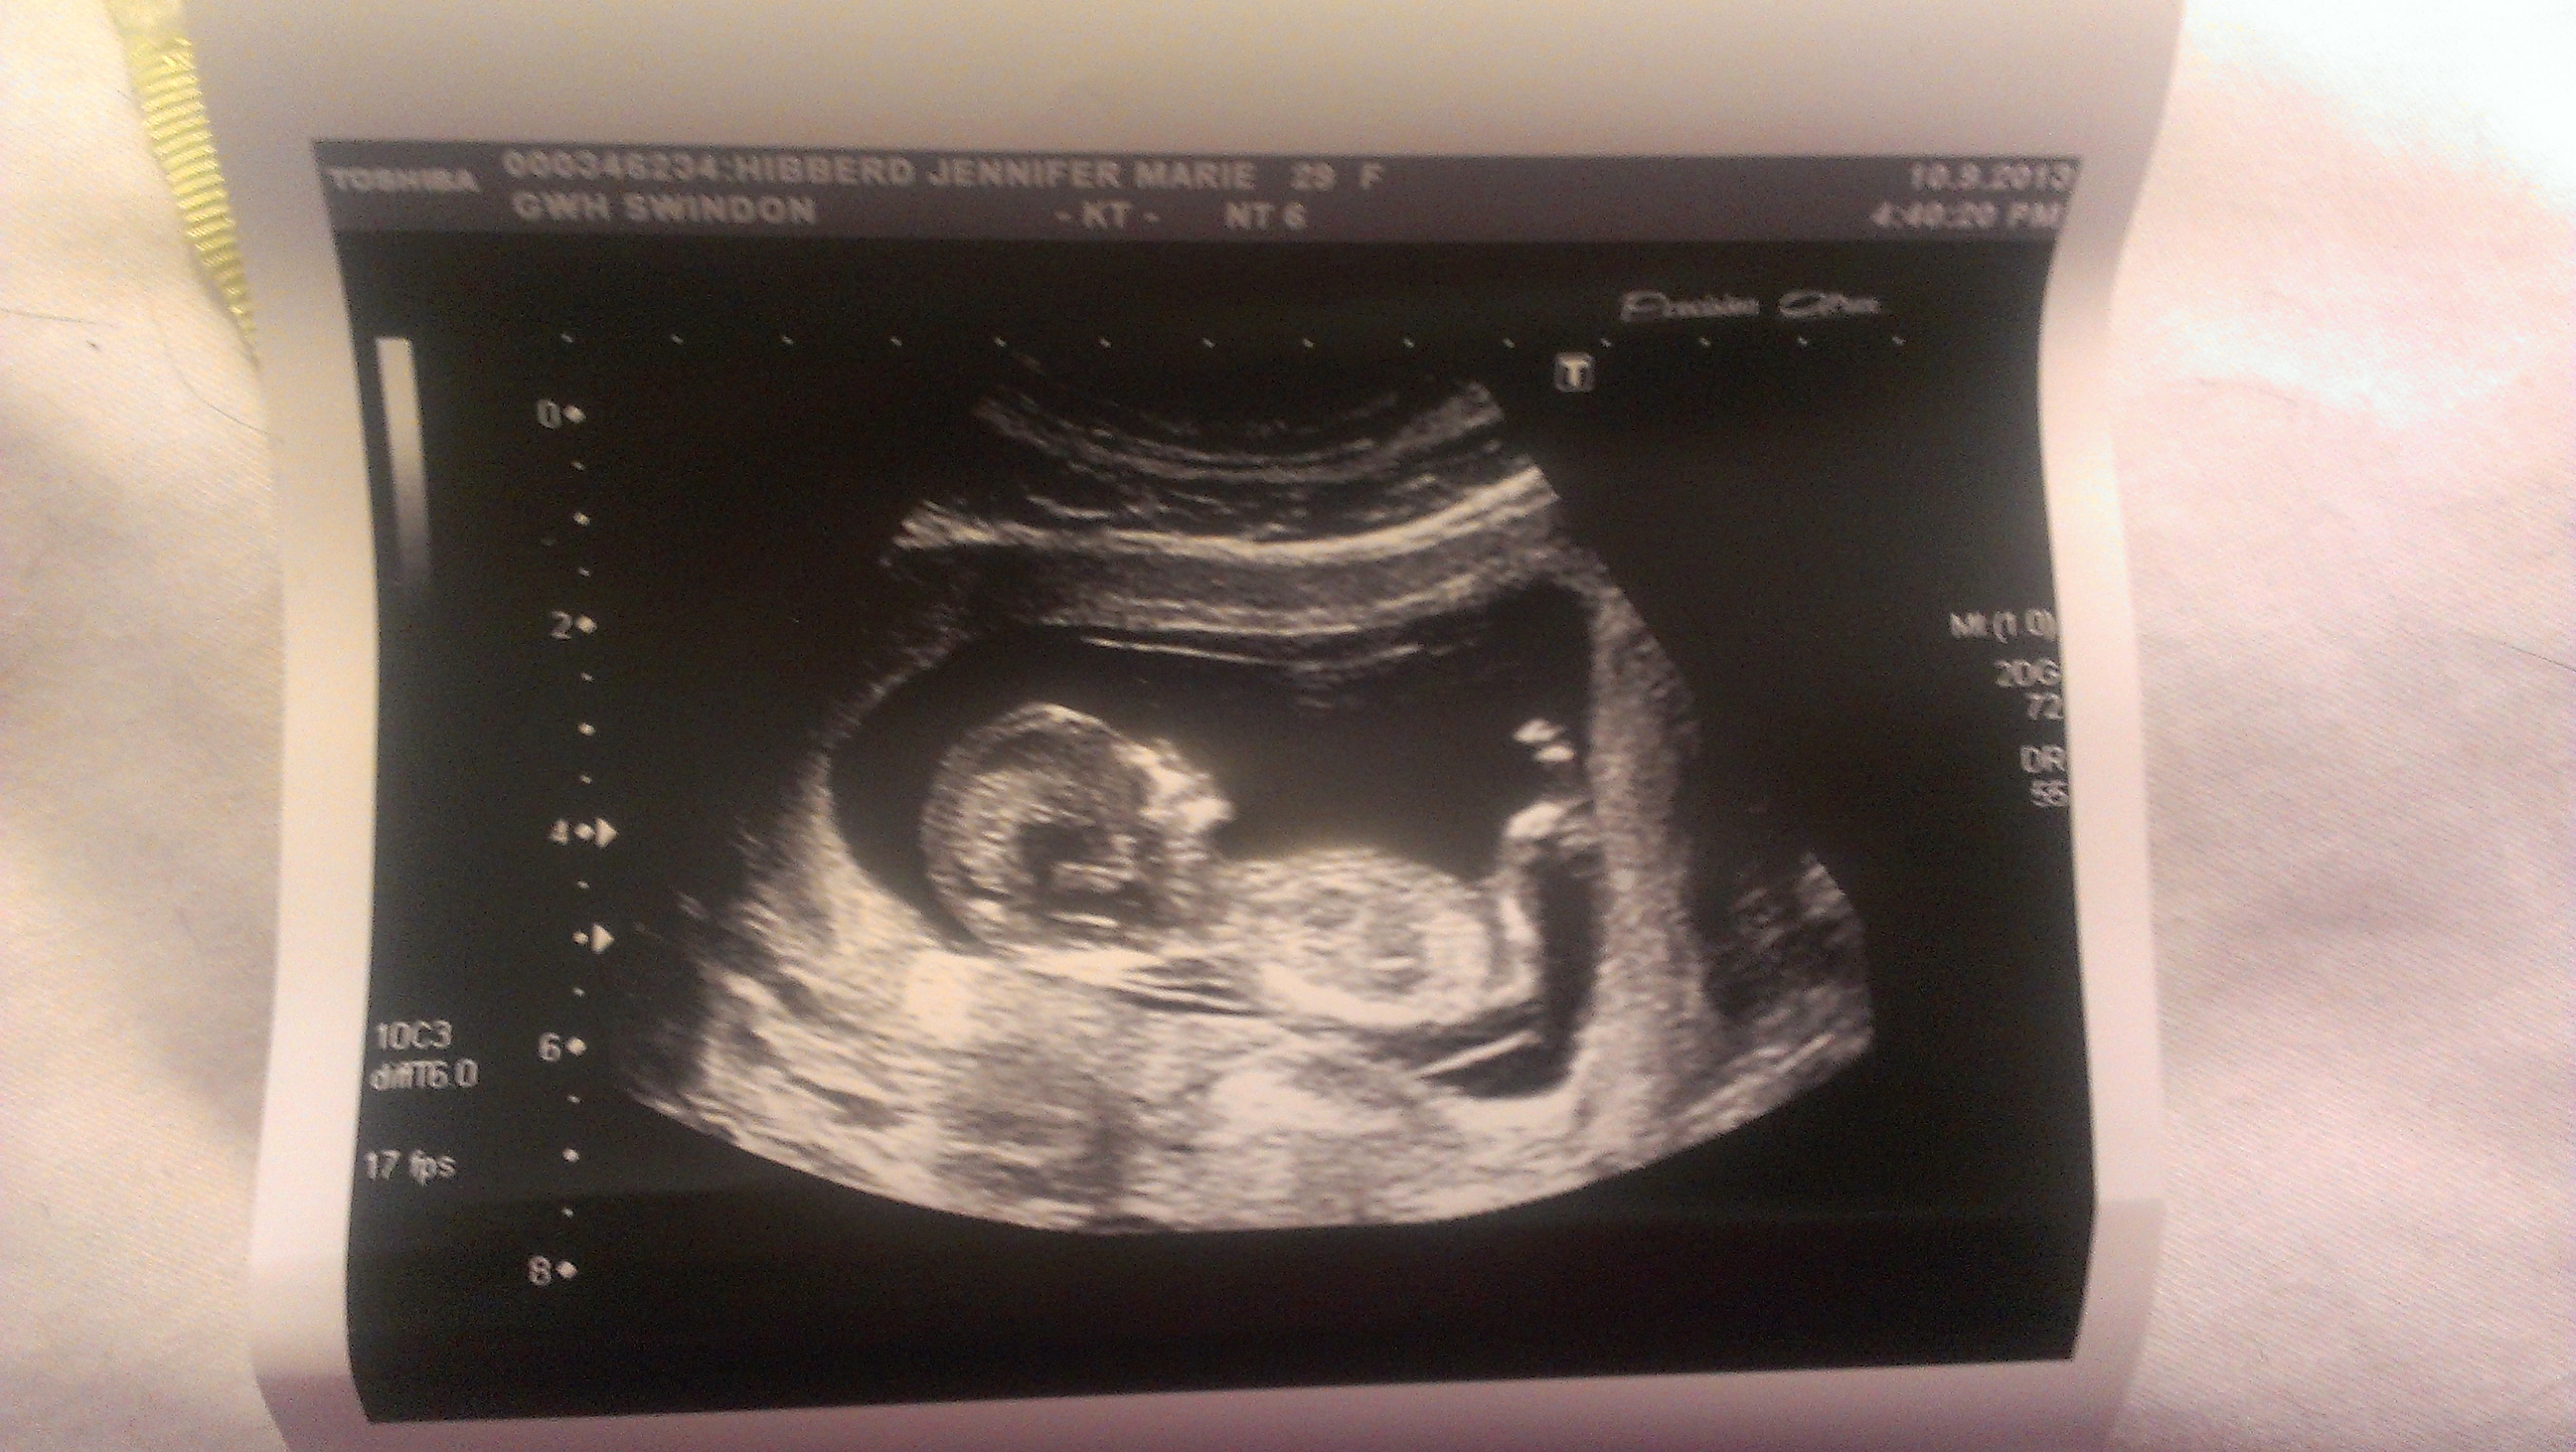

#nubtheory #boyorgirl💗💙 #6weekspregnant #12weekultrasound ...

#nubtheory #boyorgirl💗💙 #6weekspregnant #12weekultrasound ... from i.pinimg.com

12 +5 week ultrasound nub guess. Anyone know about the nub theory? Natural gender selection, ivf/pgd experts | genderdreaming.com. My mom bawled her eyes out and you can 10/10/11. But by 12 weeks this method's accuracy shot up to 98%. I got a photo from the tech and i took some screenshots from a. Check out my designer online children's. Come along as i head to the doctors for our 12 week ultrasound and noninvasive prenatal screening results.